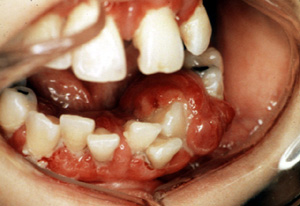

Aquí hay un

ejemplo típico degranuloma

piógeno vascular, focalmente ulcerado. Éstos son generalmente

asociados con algún tipo de irritación local; en este caso es

probablemente el aparato ortodóntico. Por el color usted puede ver que

la lesión es notablemente vascular y está casi exclusivamente

compuesto de tejido de granulación.